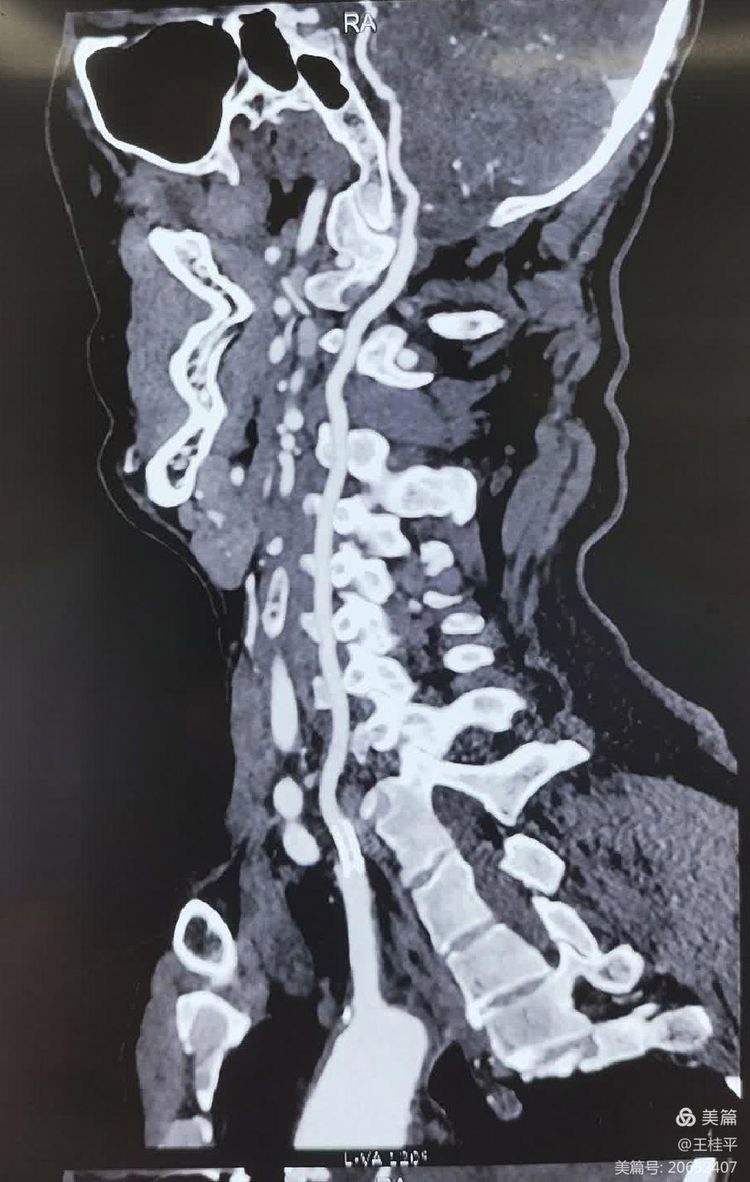

病理影响当椎动脉发生狭窄时,后脑区域的血液供应会减少,导致局部缺血小脑缺血可能引发平衡障碍如头晕步态不稳共济失调延髓缺血则可能影响呼吸心跳等基本生命功能,严重时可危及生命此外,椎动脉狭窄还可能增加脑卒中的风险,尤其是后循环梗死即脑干或小脑梗死临床表现患者可能出现。

表现椎动脉狭窄可能导致视物模糊,影响视觉功能原因缺血时,前循环受到影响,导致视物模糊严重并发症小脑梗塞脑梗死在椎动脉狭窄症状较重的情况下,患者可能出现小脑梗塞或脑梗死等严重并发症昏迷极少数情况下,椎动脉狭窄可能导致患者陷入昏迷状态总结椎动脉血管狭窄的症状多样,从。